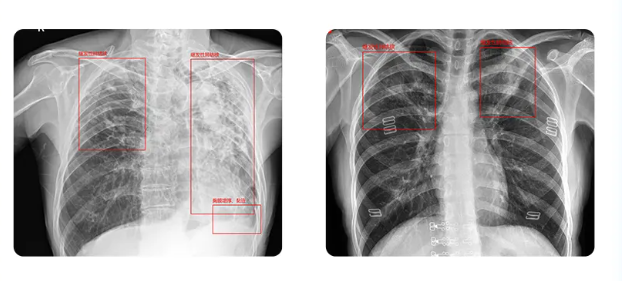

宝润便携DR+肺结核专项智能辅助诊断方案

宝润便携DR+肺结核专项AI辅助诊断方案可以帮助医生快速判断肺结核疾病。通过智能AI自动筛查精准锁定疑似结核患者,减少传播途径;防止漏诊,辅助医生做出诊断,提能增效,轻松完成大规模筛查,为社区义诊、校园筛查提供高效支持。